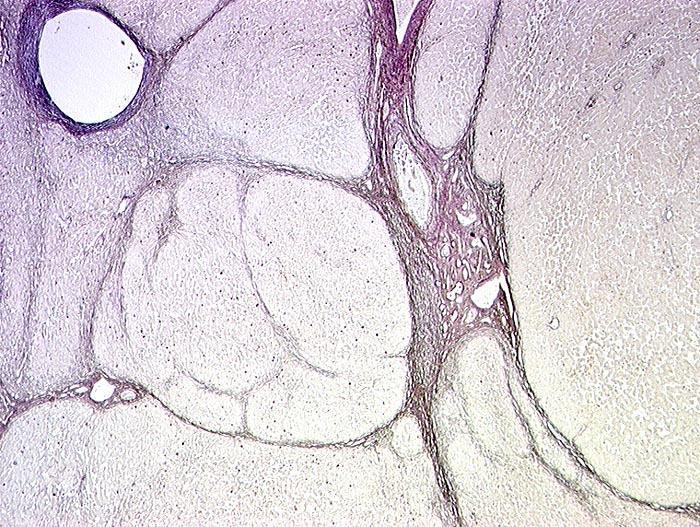

HBs Antigen positive hepatitische Leberzirrhose

Pseudolobuli ohne Zentralvenen umgeben von Bindegewebe. Kleine braune Punkte in den Pseudolobuli entsprechen Hepatozyten mit HBs Antigen.